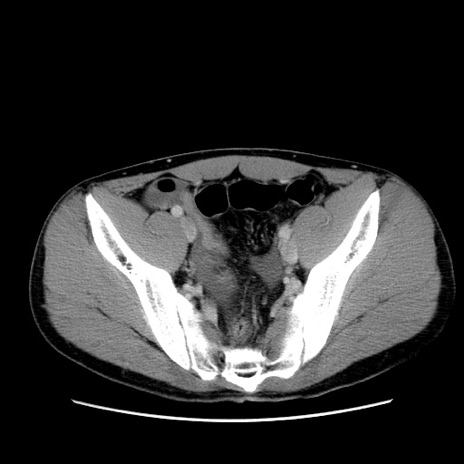

症例36(横断像)

【症例】20歳代 男性

【主訴】心窩部痛

【現病歴】今朝より上腹部痛あり。一旦軽快していたが再度出現したため救急要請。昨日夕に白身の魚を含む刺身を食べた。

【身体所見】BP 136/89mmHg、HR 74/min、BT 37.0℃、腹部:膨満、軟、心窩部に圧痛あり。反跳痛なし、筋性防御なし、腸雑音やや亢進あり。

【データ】WBC 17700、CRP 0.48